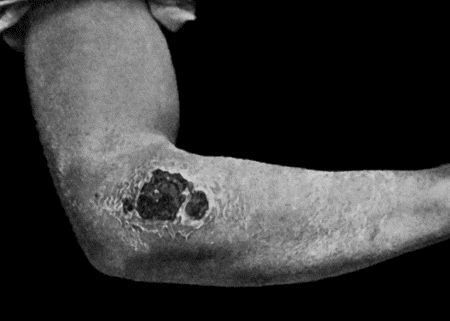

| 28. | Malignant Pustule third day after infection | 122 |

| 29. | Malignant Pustule fourteen days after infection | 122 |